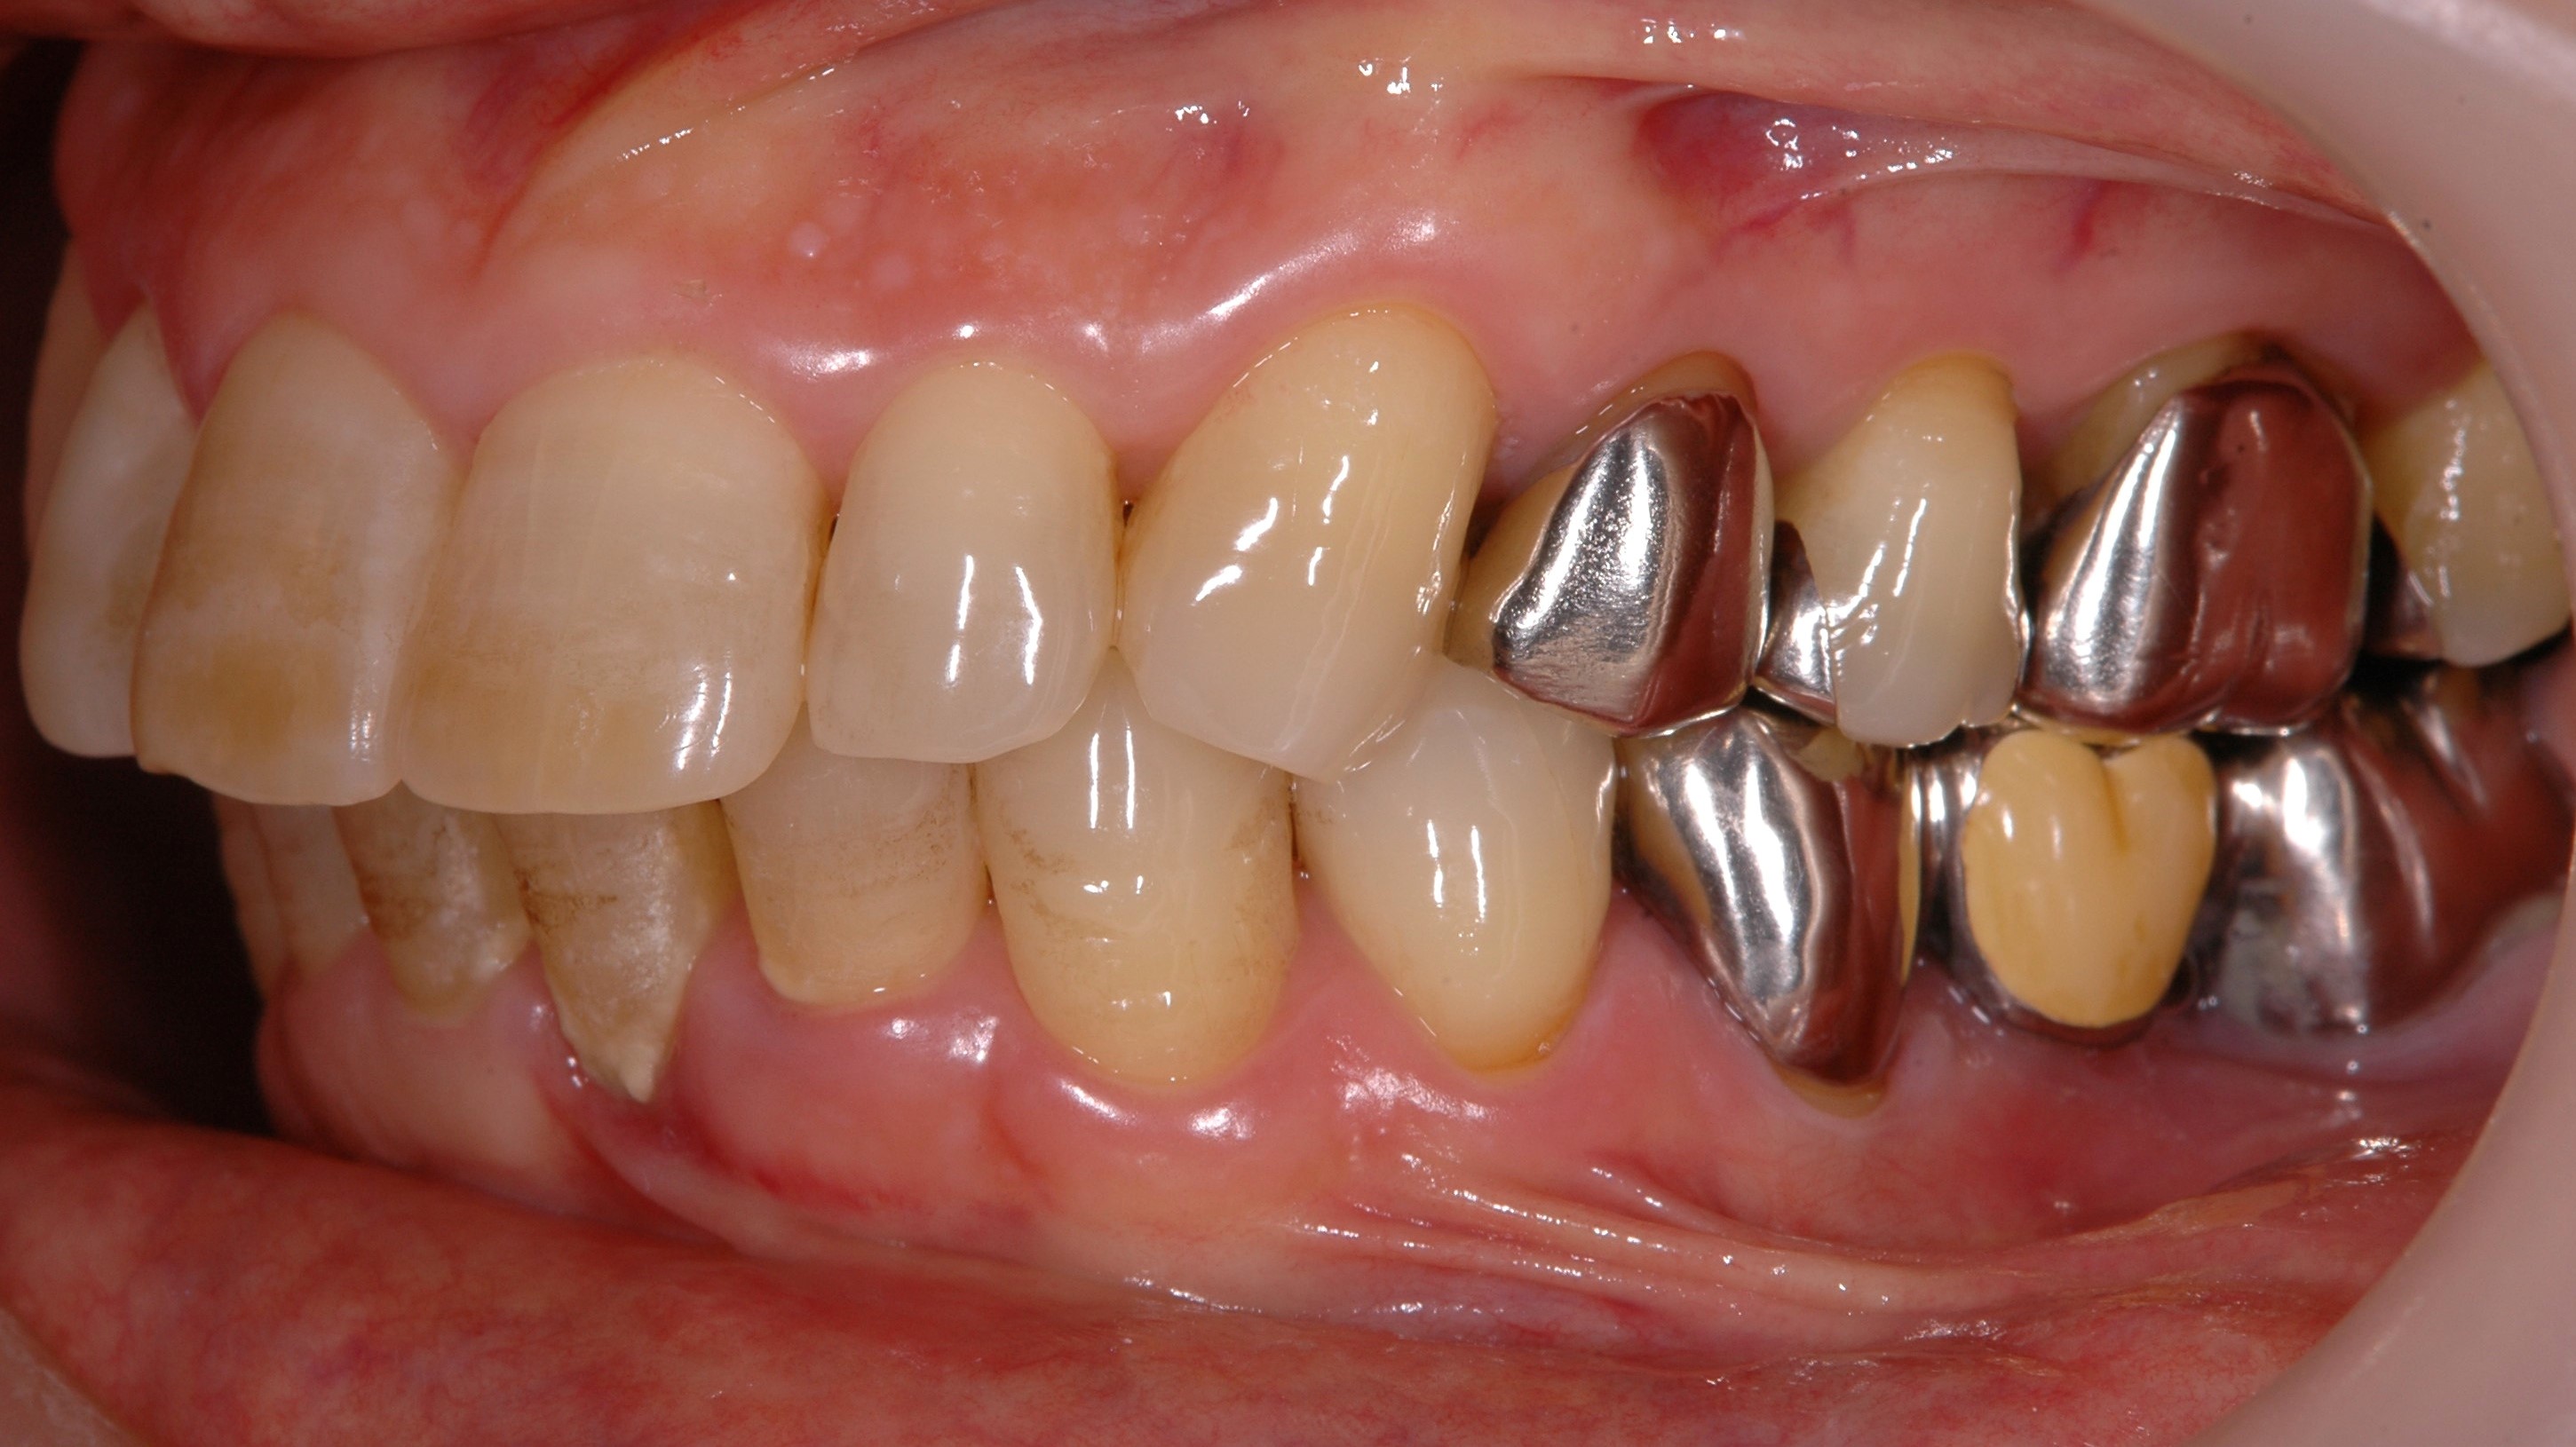

歯周病 2018.11.01 奥歯が無い方必見!奥歯の歯周病治療、歯槽膿漏って治るの?諦める前にご相談ください!! 奥歯が無い方必見!!! 先ずは以下の写真をご覧ください。 下奥歯が痛いと言って来院された患者さんです。 一件なんともなさ...